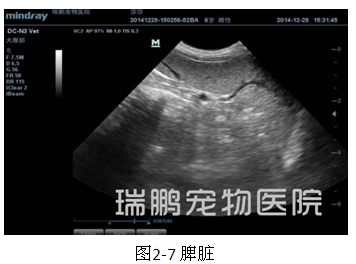

腹部超声波检查结果显示,膀胱壁回声正常、膀胱内可见一个直径约1.28 cm的高回声团块后带声影;左肾肾盂轻度扩张、肾脏结构完整、被膜完整平滑,左侧输尿管出肾门约0.5 cm处可见一个高回声团、直径约0.17 cm;右肾结构不清晰、整体回声增强 、被膜完整平滑;肝脏被膜完整平滑、肝实质回声均质、胆囊壁回声正常、胆囊内为均质无回声;脾脏回声均质、被膜完整平滑。